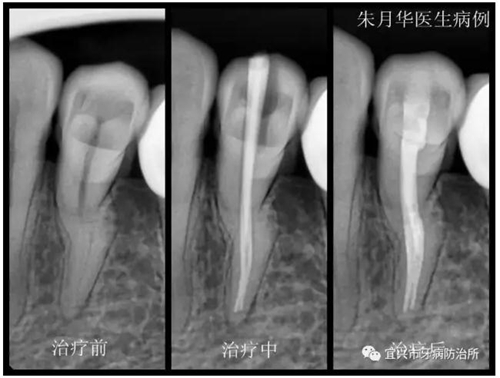

患者女,46歲,左下后牙疼痛不適數(shù)日余。經(jīng)檢查X線檢查,34根尖周牙周膜增寬,低密度影像,診斷為急性根尖周炎。處理:34局麻下開(kāi)髓揭頂,測(cè)量根管長(zhǎng)度,10號(hào)C+銼預(yù)彎在EDTA潤(rùn)滑下疏通根管,疏通至20號(hào)K銼,隨后機(jī)用鎳鈦銼根管預(yù)備,疏通及根管預(yù)備期間次氯酸鈉不斷沖洗。封氫氧化鈣,ZOE暫封。一周后復(fù)診。去凈暫封物及根管內(nèi)封藥,隔濕,紙尖干燥,大錐度牙膠尖充填,隔濕,3M自酸蝕粘接劑+3M Z350光固化樹(shù)脂充填,調(diào)合,拋光。囑忌咬硬物,不適隨診。